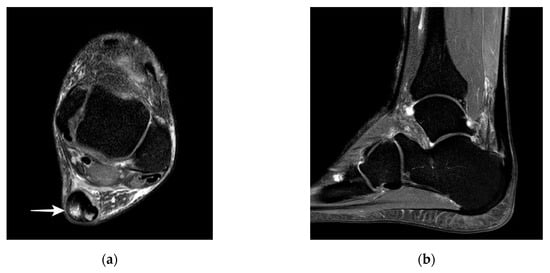

The majority of studies report that with ultrasound it is difficult to distinguish partial ruptures from focal degenerative changes, since partial ruptures appear with a wavy, irregular echo pattern with accompanying focal hypoechogenic areas, detectable neovascularization, and tendon thickening that are also findings in Achilles tendinopathy [19,23,26,28,29]. A more specific finding might be a disrupted dorsal Achilles tendon border [19,28] (Figure 2a). The detection of proximal partial ruptures close to the myotendinous junction and the differentiation between older partial ruptures and intratendinous tendinopathy are challenging with ultrasound [28,30] (Figure 2b). In MRI, a partial tear is defined as tendon thickening with a hyperintense signal on T1 and a strong hyperintense signal on magnetic resonance (MR) images with fluid-sensitive (T2-weighted and inversion recovery) sequences [29,30,31] (Figure 3). Typically, signal intensity is analogous to free fluid. A hyperintense area directly located at the tendon border should be interpreted as a partial rupture [30]. Due to muscle inactivity, isolated fatty degeneration and edema in the calf muscles might represent a subsequent state of a partial or total rupture [31]. The sensitivity of MRI in detecting partial tears is high (positive predictive value 0.94, n = 18), but studies directly comparing the accuracy of MRI and ultrasound are rare [32]. In a prospective study of Kayser et al., only one-fifth of partial lesions were noticed with B-Mode ultrasound whereas MRI detected five-fifths of partial ruptures [24].

Figure 3. MR images of partial Achilles tendon ruptures: (a) partial rupture in the dorsal part of the midportion; (b) partial rupture in the insertion. MR; magnetic resonance.